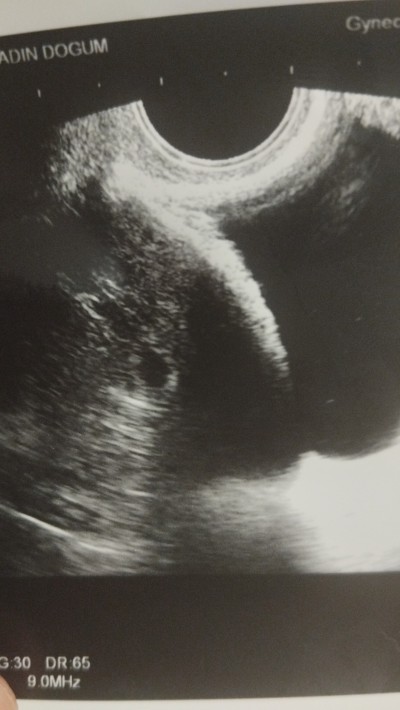

:ermm:5 haftalığım bugün sanki kese iki tane gibi ama doktor birşey demedi

Gebelik haftası 5 hafta